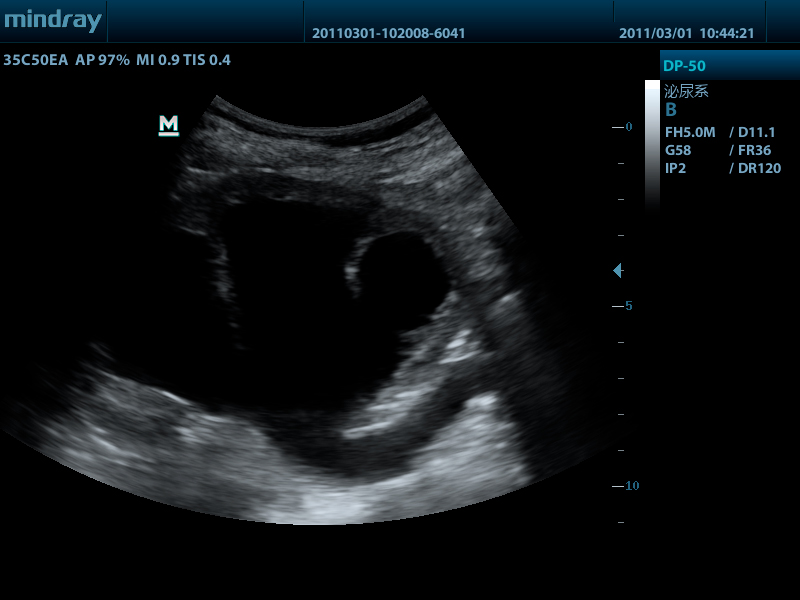

Портативный ультразвуковой сканер Mindray DP-50

Mindray DP-50 – портативная цифровая ультразвуковая система с ЖК монитором 15 дюймов (1024Х768)

и встроенными аккумуляторными батареями (опция) позволяющими работать в автономном режиме до 2-х часов.

Достоинства Mindray DP-50:

- THI - режим тканевой гармоники

- IMT автоматический расчет толщины стенок сосудов

- iTouch автоматической оптимизации изображения нажатием одной клавиши

- iClear технология подавления помех и получения четких ультразвуковых изображений высокого разрешения

- 4 USB порта: два сзади и два сбоку, Wi-Fi - беспроводная передача данных

- диапазон сканируемых частот от 2,0 до 14,0 МГц

- карты колоризации (псевдоокрашивание).

- время загрузки прибора до рабочего состояния - всего 6 с

- два порта для одновременного подключения 2-ух датчиков.

DP-50 – портативный УЗИ сканер разработан на базе новой платформы X-treme engine, используемой в хорошо зарекомендовавших себя цветных сканерах с доплером моделей DC-3, DC-7, DC-6. Эта платформа открывает возможности для расширений до уровня цветных сканеров и совместимости с широким диапазоном периферийного оборудования. X-treme означает интеллект, высокую скорость обработки данных, многоуровневую передачу сигналов, а также возможность оптимизации изображения и модульного расширения.

Применяемые датчики DP-50:

Конвексный датчик 35C50EA (2.0/3.5/4.5/5.0/Н5.0/Н6.0) R50